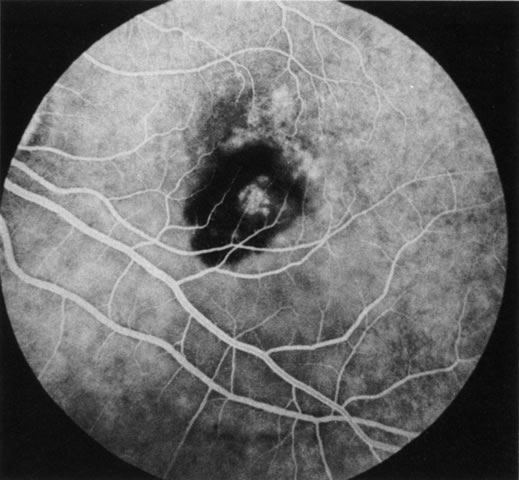

FA is generally not necessary to make the diagnosis of cystoid macular edema (CME). A history of recent cataract surgery, diabetes, uveitis, or other predisposing conditions is usually obtained. Clinically, the patient presents with retinal thickening, often with clinically evident cystic changes. FA reveals a characteristic petaloid collection of fluorescein that confirms the diagnosis, which has been shown histologically to reflect accumulation of fluid in the extravascular component of the outer plexiform layer.239 When FA demonstrates leakage from the optic nerve, this suggests an inflammatory etiology for the CME (Fig. 36). Although this sign is reliably present in CME associated with cataract surgery, penetrating keratoplasty, or posterior uveitis, it is not characteristically present in diabetics or in idiopathic CME. FA can also demonstrate dilated macular capillaries as a cause of CME in diabetes (Fig. 37). Different conditions that may cause CME include Irvine-Gass syndrome, previous penetrating keratoplasty, any inflammatory condition that involves the posterior segment, peripheral rhegmatogenous retinal detachment, peripheral cryotherapy, malignant melanoma, topical epinephrine, tapetoretinal degenerations, juxtafoveal telangiectasia, occult central retinal vein occlusion, nicotinic acid maculopathy, and idiopathic CME.

Fig. 36. Cystoid macular edema (CME). This patient had bilateral vitritis and CME. A. Early-phase photograph of the right eye reveals telangiectasia of the perifoveal retinal capillaries with some early leakage visible temporally. B. Mid-phase photograph of the left eye reveals more intense fluorescence leakage. C. Late-phase photograph of the left eye demonstrates cystic accumulation of fluorescein in a classic “petaloid” configuration. The late-phase staining of the optic nerve head in this fluorescein angiogram suggests an inflammatory cause of the CME.